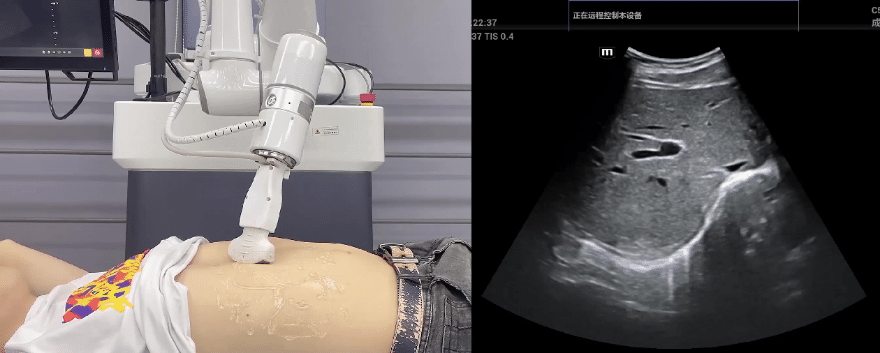

艾利特協作機器人搭載庫柏特自主研發的機器人遙操作、多模態數據采集與處理、機器人模仿學習、機器人力位控制等技術升級變革傳統超聲,可實現遠程+自主超聲掃查與診斷,從傳統遠程超聲僅能對話會診變革升級為能對話、能操作,使得基層患者可就近享受異地三甲專家掃診服務。實現專家端與患者端遠程連接,并支持專家端與多路患者端自由切換控制。

艾利特機器人末端搭載超生L13-3N線陣探頭,可以對淺表小器官和外周血管進行超聲檢查;搭建C5-1s凸陣探頭,可以對腹部(肝、膽、胰、腎等器官進行超聲檢查)

EC66協作機器人末端可搭載主流品牌高品質超聲儀,讓操作指令和影像低延遲、高精準、高保真傳輸,確保檢查可靠、醫患放心;智能力控等三重防護系統,確保患者舒適、安全。

艾利特協作機器人與超聲深度打通,最大程度保留醫生左右手同時操作傳統超聲的習慣,并改善其舒適性,超聲檢查實際應用場景展示如下: